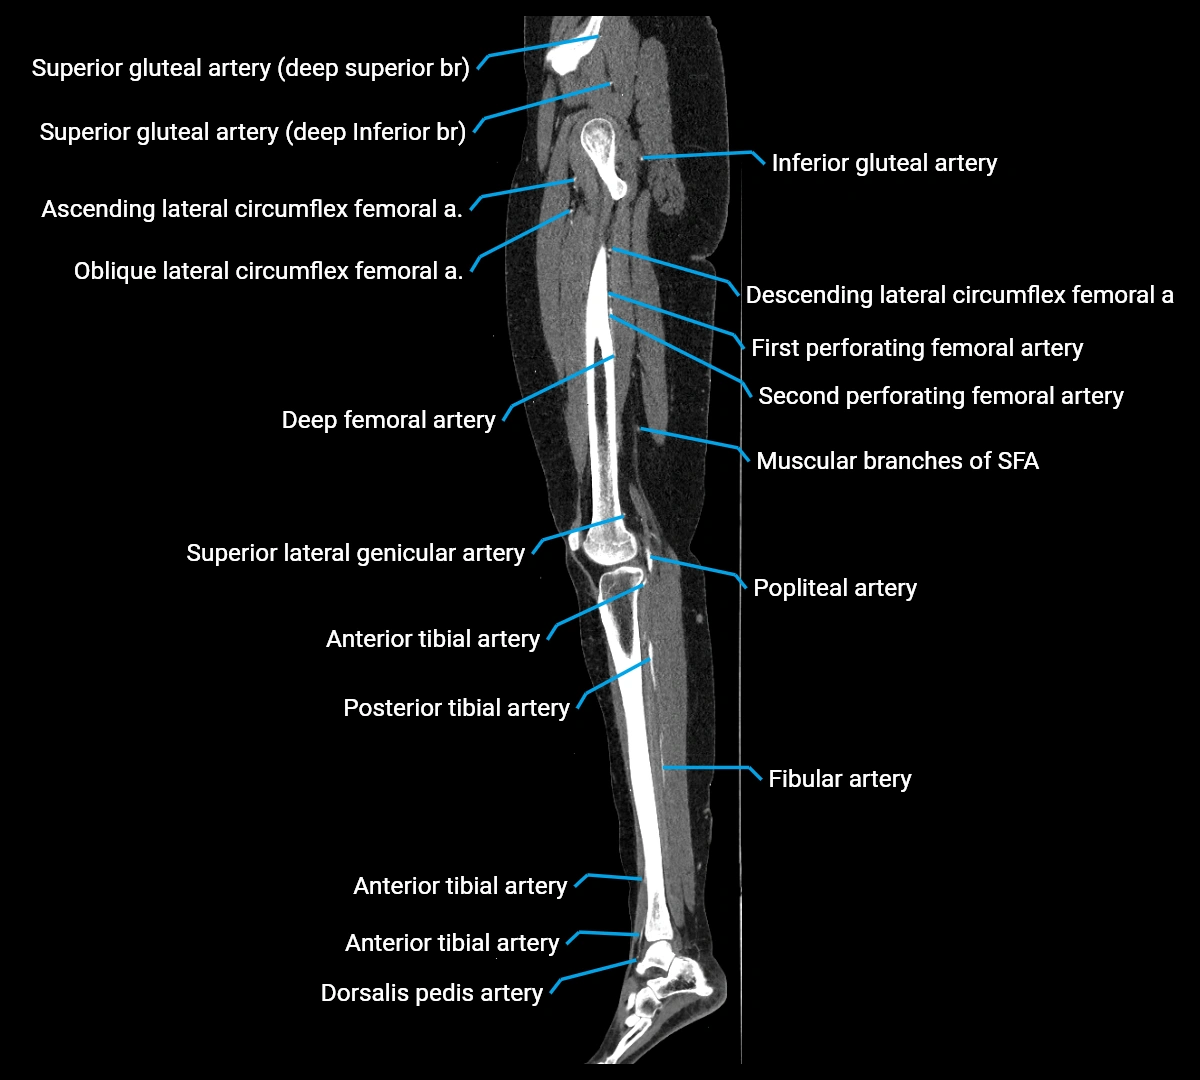

Contrast-enhanced CT (CTA):

• Gold standard for abdominal aortic imaging

• Provides excellent detail of lumen, wall, aneurysm, thrombus, and branch vessels

• Multiplanar and 3D reconstructions help in aneurysm measurement, stent graft planning, and dissection evaluation